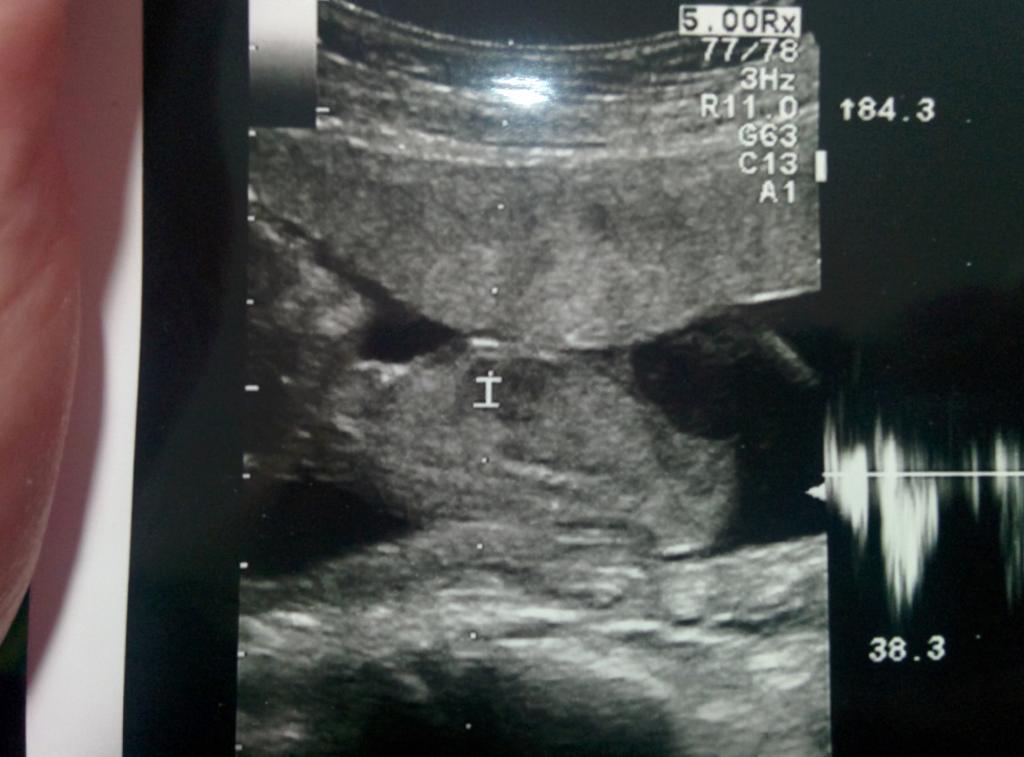

I have no clue if the nub is visible and where in my 11 week 4 day scan. Could anyone help me out? And if you see the nub, could you tell me where it is and whether it points to girl or boy? I would be very grateful for your help!

Attachment 23701Attachment 23702